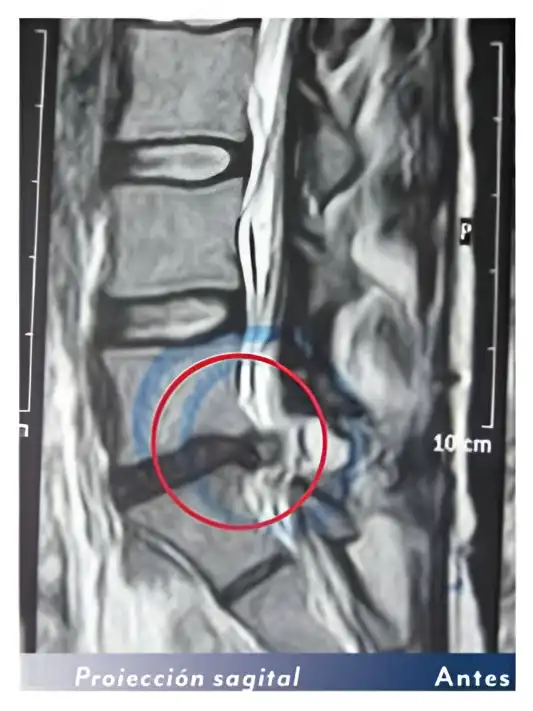

Las resonancias de un paciente antes y después de las sesiones con la bomba diamagnética. El paciente ha realizado 15 sesiones de bomba diamágnetica. Después la hernia discal ha desaparecido.

Otro ejemplo: Antes y después de 15 sesiones con la bomba diamagnética.

La hernia grande (extruida) ha desaparecido del todo (100%)